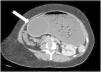

A 45-year-old woman came to the emergency service due to 3 days of ongoing vomiting and significant generalized and progressive abdominal distension. Her past medical history was unremarkable, except for the placing of an intragastric balloon 3 weeks prior. Plain abdominal x-ray revealed an occupied abdomen and bowel loop displacement toward the periphery. A computed axial tomography scan identified severe dilation of the gastric corpus, along with the intragastric balloon (white arrow), which was embedded in the antral region, causing the gastric outlet obstruction (Figure 1 in the axial plane, Figure 2 in the sagittal plane, and Figure 3 in the coronal plane). According to the medical literature, frequency of overall complications from intragastric balloon placement reaches 2.6% and obstruction is one of the most common causes in the early postoperative period, with a frequency of 0.8%. First, a nasogastric tube was placed in our patient to relieve the distension, after which the obstruction was resolved through endoscopic removal of the balloon. After the intervention, the suggested cause was the progression of the balloon and its lodging in the antrum of the stomach, with no excessive filling of that gastric region.